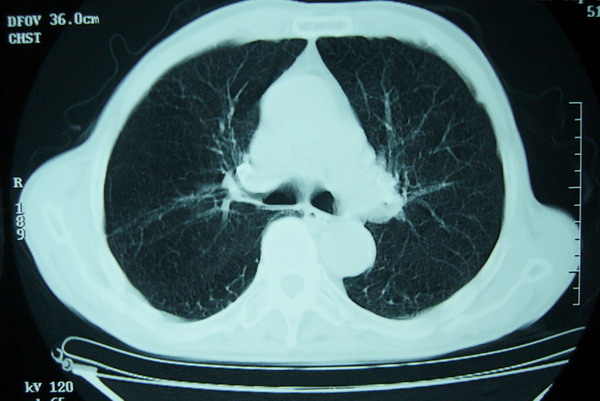

标题: CT15579:男 86岁 咳嗽 咳少量白痰 发热2天 吸烟史60年 [打印本页]

标题: CT15579:男 86岁 咳嗽 咳少量白痰 发热2天 吸烟史60年

右上周围型肺癌,慢支,肺气肿。

分叶及少量边缘性钙化,老年人,周围性肺癌首先考虑。

右上肺一不规则团块,边缘有分叶和毛刺,纵隔有淋巴结肿大。右肺周围性肺癌首先考虑。